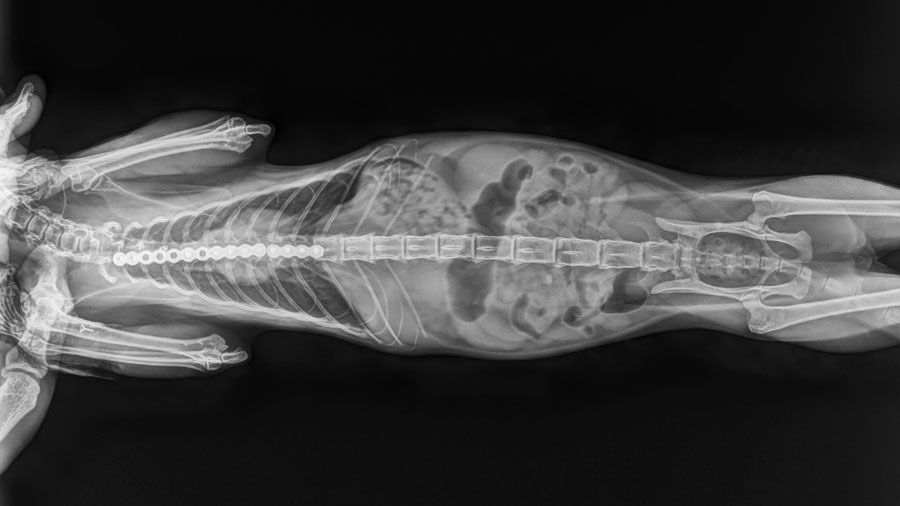

When I met the owners, they had simply come in seeking another temporary relief. But after examining the cat and reviewing the imaging— X-rays during inspiration and expiration showed just how dramatically the chest wall collapsed with every breath—I knew this wasn’t just a case for palliative care. It was a candidate, albeit a risky one, for surgical intervention.

Instead of trying to follow an existing formula, we built our plan around the cat’s unique anatomy. Using X-rays and video studies, I identified the "breakdown points" in the chest wall—the areas of maximum inward deviation and instability. I noted which costal cartilages were contributing to the deformity and which vertebral sternal segments were overly flexible or weak.

Our surgical plan was to remove the influence of the problematic ribs by severing their connection to the sternum. We would then reinforce the weakened sternal segments with a bent titanium reconstruction plate, designed to mimic the natural contour of a healthy sternum. It wasn’t a fancy, custom 3D-printed solution—we don’t have that capability here—but it would be strong enough and adaptable enough to offer real structural support.

Over the next 10 days, we kept the cat hospitalized, providing antibiotics, anti-inflammatory medications, and close observation. There were no signs of infection, no implant rejection, no respiratory distress. Follow-up X-rays over the next few months confirmed that the plate remained intact, and the chest structure was stable. Even better, the cat gained 50% of its body weight in three months, a sign not just of recovery but of thriving.